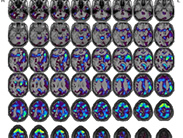

MRI検査

MRIはMagnetic Resonance Imaging (磁気共鳴画像)の略で、強力な磁石の力で体の内部を画像化する装置です。一般撮影検査やX線CT検査などと異なり、放射線を使用しないため被ばくがなく、何回検査をしても体に悪い影響はありません。ただし道路工事をしているような大きな音がしたり、検査室内に金属が持ち込めない等の制限があります。けがの治療などで体内に金属を入れている方は事前にご相談ください。

当院では3.0テスラMRI装置と1.5テスラMRI装置が稼働しています。

- ・脳神経外科領域

- MRIが最も得意とする部位で、頭の血管の描出や脳梗塞、認知症の検査が可能です。予防医学センターでは脳ドックも行っております。